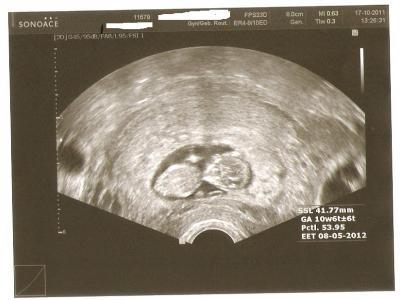

und es ist alles super! baby ist 4,2 cm groß und putzmunter. Mutterpass hab ich auch bekommen und darf dann in 4 wochen wieder hin. ET ist laut US immernoch der 8.5. aber der Arzt hat in den Pass jetzt den EET reingeschrieben also der 11.5. was mir aber auch wurscht ist :) kommt eh wanns will..... lg carina

Bild zu auch ich war heut beim arzt - Forum für Mai - Mamis